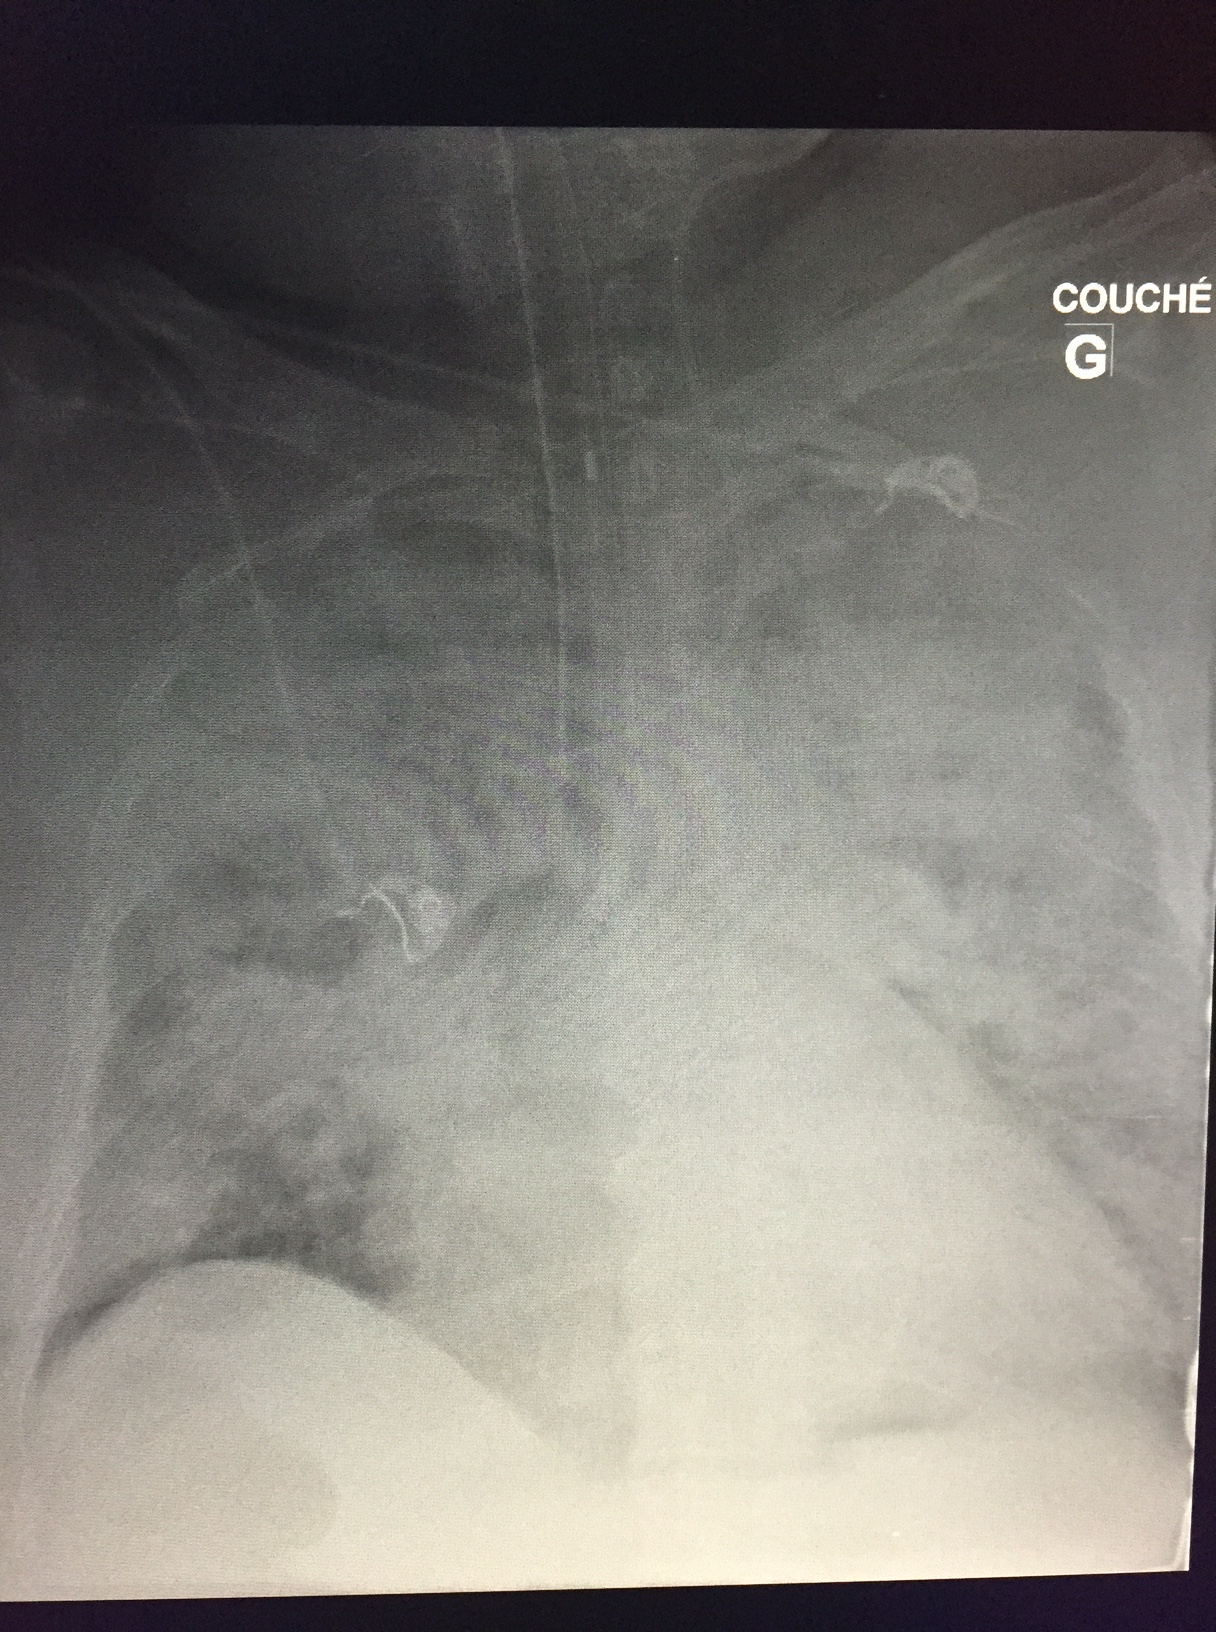

So a couple weeks ago I saw a patient in the ED who’d recently broken an ankle, had her foot put in a boot and managed conservatively and came back dyspneic and tachycardic. Here are a couple of clips:

She wasn’t very echogenic so I don’t have great clips of the heart but she had a dilated and hypocontractile RV with a McConnell’s sign (preserved apical contraction), small and hyper dynamic LV with septal flattening.

Based on hemodynamics, tachypnea and, to some degree, venous congestion, I decided to thrombolyse her using 1/2 dose lytics. Within a couple of hours her HR decreased to the 90’s and BP rose to 110 systolic. Echographically, however, the IVC/RV findings remained similar, but the HPVG decreased. By the next day, HPVG was altogether gone, lactate had resolved and dyspnea was significantly better.